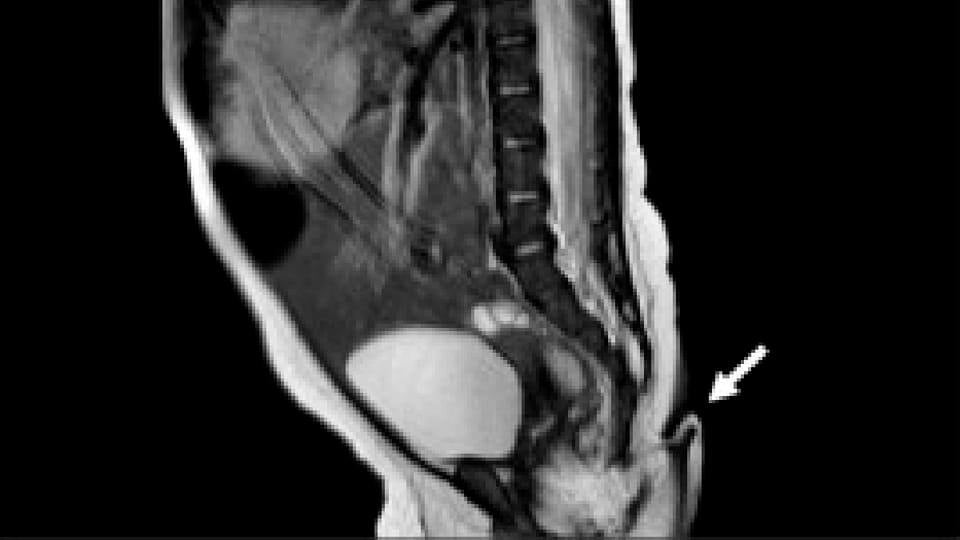

Segundo o site Infobae, o caso aconteceu na área rural de Nuevo Léon, no México. De acordo com os médicos, o bebê é uma menina e a saúde está em dia, porém foram realizados exames para avaliar a cauda, que nasceu em seu cóccix.

Tanto a mãe quanto o bebê estão com boa saúde, mas a equipe médica se dedicou a identificar do que se tratava a condição. Foram realizados exames para identificar se o membro possuía conexões nervosas. Ao colocar uma agulha na cauda, a menina começou a chorar.

Os médicos recomendaram que os pais continuassem acompanhando o bebê em casa, mas solicitaram uma consulta mensal. Com dois meses de idade, os especialistas notaram que a cauda, que era lisa, coberta de pelos finos, sem cartilagem ou ossos, começou a crescer. Sendo assim, uma cirurgia de remoção foi recomendada e a operação foi realizada sem maiores problemas.